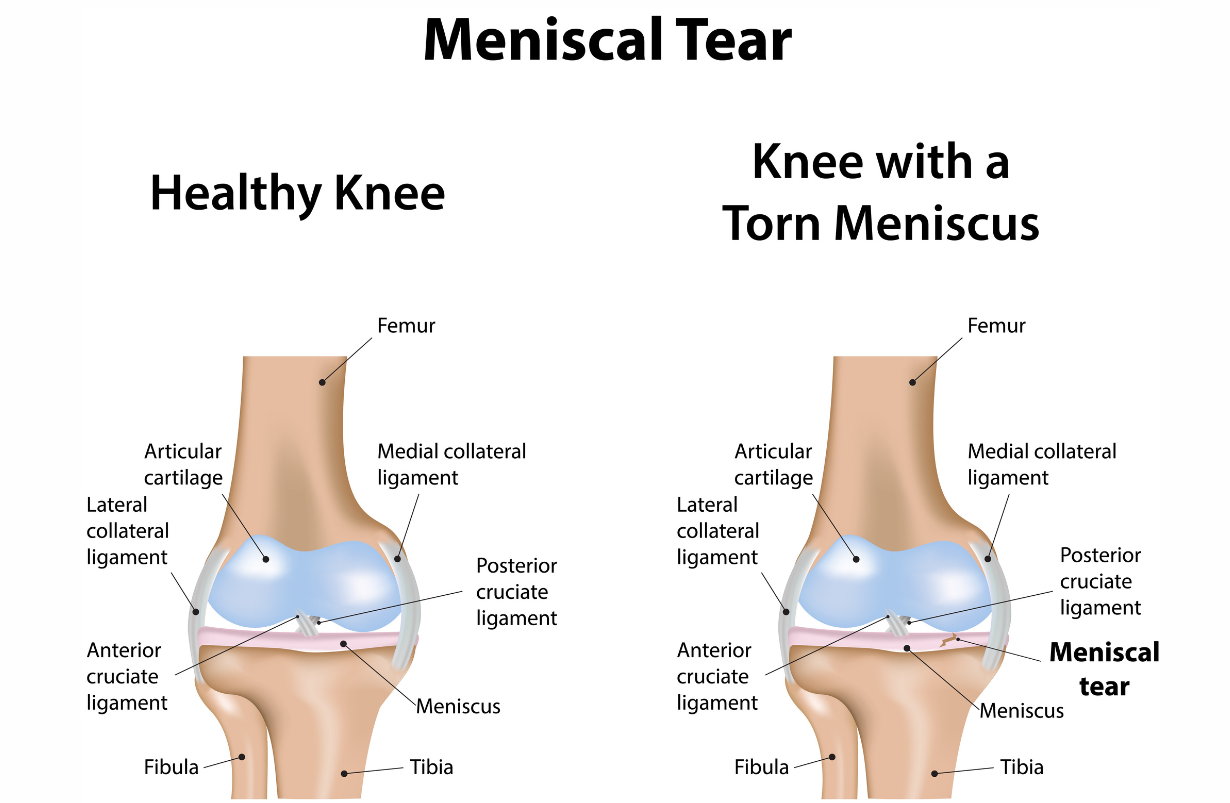

Lateral Meniscal Tear

Tear in the outer cartilage of the knee that cushions the femur as it presses down on the tibial plateau, e.g., in walking. This typically occurs with twisting injuries of the knee. For example it could happen to the right knee if the leg were externally rotated, and a player were tackled from the right side. Radiograph from Wikipedia.

Medial Meniscal Tear

Tear in the inner cartilage of the knee that cushions the femur as it presses down on the tibial plateua, e.g., in walking. BENEFICIAL POSES: Dandasana, Vasisthasana, Paripurna Navasana, Ardha Navasana. EXPLANATION: These poses activate and strengthen the vastus lateralis, the most lateral of the four muscles that form the quadriceps. If it can be made to work more strongly, it will mildly tilt the femoral condyles laterally, away from the medial meniscus, REFERENCE: Kise NJ, Risberg MA, Stensrud S, Ranstam J, Engebretsen L, Roos EM. Exercise therapy versus arthroscopic partial meniscectomy for degenerative meniscal tear in middle aged patients: randomised controlled trial with two year follow-up. BMJ. 2016 Jul 20;354:i3740. doi: 10.1136/bmj.i3740.